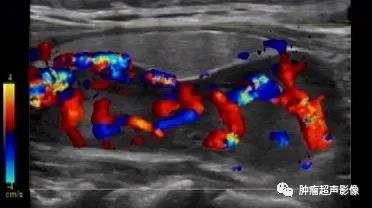

病理证实的甲状旁腺腺瘤:位于甲状腺背侧,完整的包膜,呈低回声,血流丰富呈瀑布样,符合典型的甲状旁腺腺瘤。